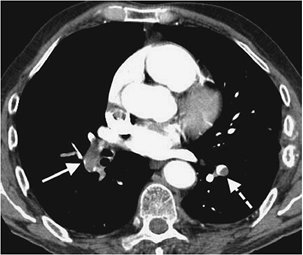

FIGURE 17-13. Chronic PE. A: PA chest radiograph of a 43-year-old woman with recurrent DVT and PE for 20 years shows a small right pulmonary artery and diminutive vessels in the right upper lobe. B: CTPA shows a small irregular right pulmonary artery with residual clot and areas of recanalization (solid arrow) and bronchial artery collaterals (dashed arrow). C: CTPA at a more inferior level shows additional bronchial artery collaterals in a paraspinal and subpleural location (arrows). The main pulmonary artery (PA) is markedly enlarged. D: CTPA with lung windowing shows small right pulmonary arteries and a mosaic pattern of lung attenuation.